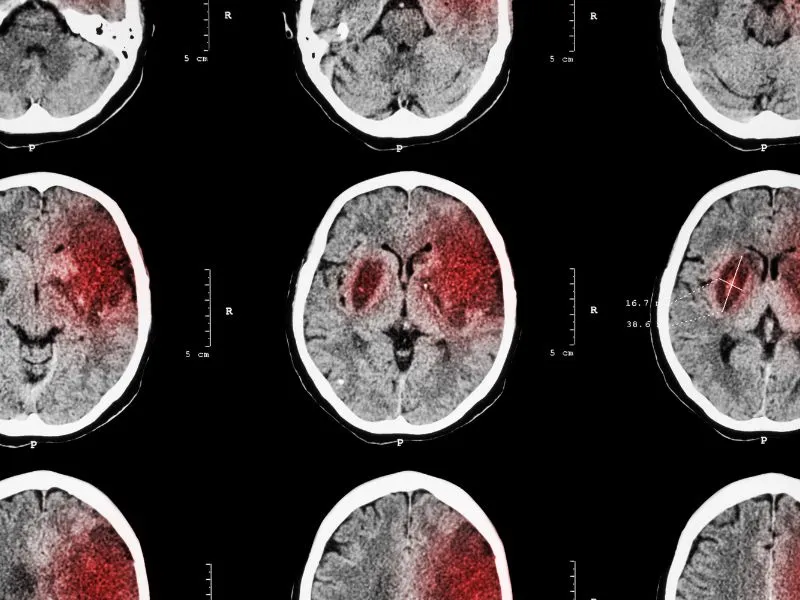

Udar mózgu to poważny stan zdrowia, który często mylnie kojarzony jest wyłącznie z osobami starszymi. Jednak, jak pokazują statystyki, może on wystąpić również u młodszych pacjentów, w tym osób w wieku 20-35 lat. Około 5% wszystkich przypadków udaru dotyczy ludzi młodych, a ryzyko znacznie wzrasta w przypadku obecności czynników ryzyka, takich jak nadciśnienie tętnicze, palenie tytoniu czy miażdżyca. W artykule omówimy, w jakim wieku można się spodziewać udaru, jakie czynniki mogą wpływać na jego wystąpienie, a także jak rozpoznać objawy i jakie działania profilaktyczne można podejmować, aby zminimalizować ryzyko.

Udar mózgu to poważna choroba, która może dotknąć ludzi w każdym wieku. O ile jest powszechnie postrzegany jako schorzenie osób starszych, coraz częściej występuje także u młodszych pacjentów. Statystyki pokazują, że udział młodych ludzi w przypadkach udaru wynosi około 5%, co czyni ten problem istotnym również w kontekście zdrowia publicznego.

Współczesne badania wskazują, że udar w młodym wieku jest zjawiskiem, które zyskuje na znaczeniu. Około 10% udarów dotyczy osób poniżej 50. roku życia, co jest alarmującym sygnałem i powinno zwrócić uwagę zarówno pacjentów, jak i lekarzy. Z kolei dla osób starszych, w szczególności powyżej 55. roku życia, ryzyko znacznie rośnie, a czynniki takie jak nadciśnienie czy miażdżyca stają się kluczowe.

Objawy udaru niezależnie od wieku

Objawy udaru są niemal identyczne niezależnie od wieku pacjenta. Kluczowe jest ich szybkie rozpoznanie, co może uratować życie lub zminimalizować skutki udaru. Należy zwrócić uwagę na:

- Niewyraźną mowę.

- Osłabienie kończyn po jednej stronie ciała.

- Zaburzenia równowagi.

- Problemy z rozumieniem mowy (afazja).

Znaczenie szybkiego działania w przypadku udaru

Szybka reakcja na objawy udaru jest kluczowa. Im szybciej udzielona zostanie pomoc medyczna, tym większe szanse na pomyślne leczenie i minimalizację skutków. Należy jednak pamiętać, że brak działania może prowadzić do poważnych konsekwencji, w tym trwałego uszkodzenia mózgu lub nawet śmierci.

Każda minuta ma znaczenie, dlatego ważne jest, aby osoby znajdujące się w pobliżu chorego potrafiły zidentyfikować objawy i natychmiast wezwały pomoc. Uświadomienie sobie tej potrzeby może uratować życie.